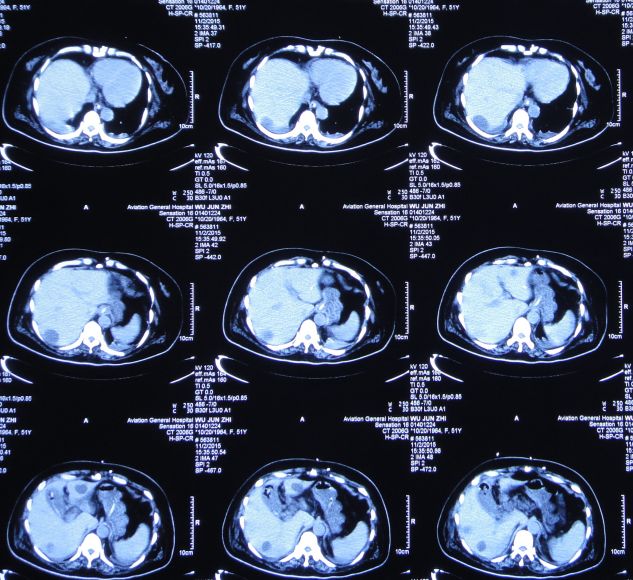

当日上午患者诉上腹部、下胸部疼痛。急查腹部CT:肝内多发囊肿;胆囊结石、胆总管结石(图32)。

图32:2015年10月27日腹部CT肝内多发囊肿;胆囊结石、胆总管结石

ERCP术后第一天即2015年10月30日,患者症状仍无改善,精神差,呼吸急促,喘憋,张口呼吸,言语不清,持续胃肠减压。白细胞:19.3*10^9/L↑,中性细胞比率:94.0%↑,血红蛋白:74g/L↓,血小板:51*10^9/L↓,白蛋白:26.3g/L↓。急查腹部CT:胆囊增大、胆囊结石。

图34:2015年10月30日腹部CT:胆囊增大、胆囊结石

胆囊造瘘术后第3天即2015年11月2日,患者神志朦胧,发热,最高T39.0℃;查胸CT:双肺感染(图36)。查腹部CT:胆囊造瘘术后改变,胆囊较术前缩小,无结石影(图37)。

图37:2015年11月2日腹部CT:胆囊较术前缩小

胆囊造瘘术后第17天即2015年11月16日,患者神清,仍间断呕吐;查腹部CT:与2015年11月2日腹部CT比较:1.胆囊内高密度影消失,壁模糊。2.肝内多发囊肿较前无明显变化。3.腔静脉支架术后改变(图39)。

图39:2015年11月16日查腹部CT

胆囊造瘘术后第56天即2015年12月25日,复查头CT:颅内无异常(图44)。查腹部CT:胆囊造瘘术后,改变(图45)。

图45:2015年12月25日腹部CT:胆囊造瘘后改变

查腹部CT:胆囊切除术后改变,无明显异常(图53)。

图53:2016年1月30日腹部CT:胆囊切除术后改变,无明显异常